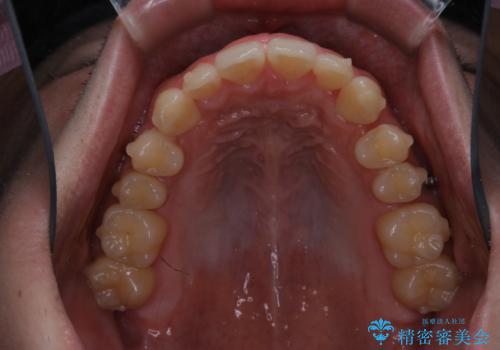

- 上の前歯が見えすぎて気になるとご相談にいらした方です。インビザラインにて前歯の圧下を行うことで歯の見え方の改善し、同時に奥歯の噛み合わせも改善を行いました。

インビザラインを正しく使用して頂けたおかげで、比較的難しいとされる歯の圧下も補助装置を使用せずに行うことが出来ました。上の前歯のラインが整ったことで笑った時の口元の印象を改善させることができ、大変喜んでいただけました。